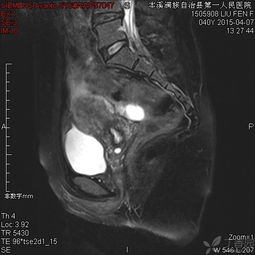

6、盆腔內(nèi)病變:包括膀胱、前列腺、子宮、卵巢、直腸良、惡性占位病變,特別是前列腺增生,子宮內(nèi)膜異位癥等。MRI多方位、大視野成像可清晰地顯示盆腔的解剖結(jié)構(gòu)。尤其對女性盆腔疾病具有重要診斷價值,對盆腔內(nèi)血管及淋巴結(jié)的鑒別較容易,是盆腔腫瘤、炎癥、子宮內(nèi)膜異位癥、轉(zhuǎn)移癌等病變的最佳影像學(xué)檢查手段。